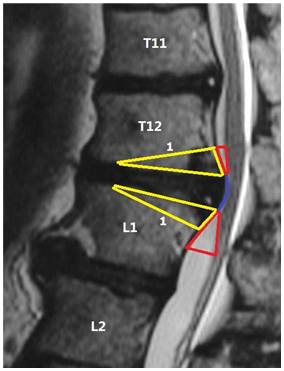

2. 手术方法:所有手术均在气管插管全麻下进行。麻醉满意后将患者置于俯卧位,胸前及双髂前垫枕,腰部稍后弓,腹部悬空。(1)手术切口和显露:依体表解剖标志结合影像学定位或体表放置金属标志行透视定位,来确定手术节段平面之所在;以此为中心行皮肤纵行切口,切口长度以分别包括头、尾侧的1~3节椎骨为宜。骨膜下剥离显露棘突、双侧椎板、关节突关节或肋横突关节和横突。(2)椎弓根钉道准备和螺钉植入:于椎间盘突出的相邻椎节,常规方法置入固定用的椎弓根螺钉,并经术中透视核实其固定节段无误且位置良好。(3)椎管后壁切除及后方椎间盘切除术:于双侧关节突关节的中线处纵向开槽,使用高速磨钻逐步向前磨透骨性结构,将椎管后壁以“揭盖式”整块切下。若同时还合并有黄韧带骨化,则一并予以切除。然后,以神经拉钩轻轻将硬膜牵向对侧,常规方法行突出椎间盘的后外侧纤维环切开、髓核摘除。此时,切记不要勉强行突出于硬膜腹侧正中部分的椎间盘切除,以免在切除过程中造成硬膜和神经的损伤。(4)极外侧入路:行残余的关节突关节切除后,充分显露突出椎间盘椎间隙的外侧缘,保护好椎间孔内穿行的神经根。在“安全三角区”(图1a, 1b)内,尽可能以与脊柱矢状面相垂直的方向经突出椎间盘的正侧方行椎间隙内残余的椎间盘组织切除。此时,尤其是合并“硬性突出”的椎间盘已呈一中空的“硬壳”,使用窄的快骨刀切断“硬壳”的基底部(即与椎体相连处),再以神经剥离子仔细分离其与硬膜间的粘连,将该游离“硬壳”轻轻压陷至已被掏空的椎间隙内,用髓核钳将其取出。如果对侧尚有残留的“硬壳”,同法处理对侧,完成彻底减压。(5)椎体间融合及椎弓根固定:将减压过程中切下的骨质经修理后植于椎体间,同时放置充填好碎骨的肾形椎间融合器(TLIF Cage)一枚。再次术中透视核实Cage位置无误后,遂经椎弓根螺钉行脊柱后方加压,一方面夹紧椎间融合器,同时也纠正了脊柱局部的后凸角度,进而达到椎管内神经结构的二次减压功效。

图1a 经后方极外侧入路手术横截面示意图,阴影部分为传统正后方切除范围,红色区域为改良手术增加切除范围,曲线1为突出椎间盘,曲线2为向后牵拉之胸膜,箭头a为手术入路方向,箭头b,c所示为间盘切除方向

图1b. 经后方极外侧入路手术矢状位示意图,红色区域为“安全三角区”,黄色区域为手术操作切除区域,直线1为楔形截骨线